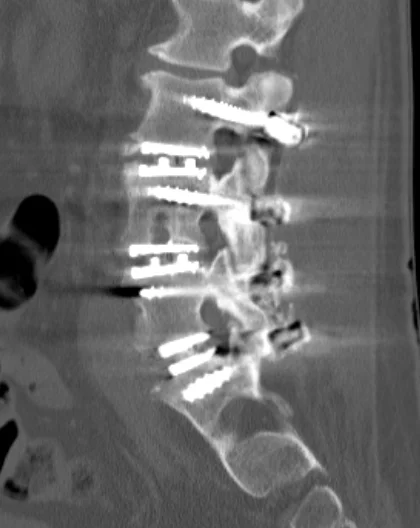

Det stämmer. Bröt vänster höft 2018 när jag låste upp bakbromsen i en serpa och trillade på sidan. Sen fick jag nekros i den höften så det sattes in protes. Tyvärr på dåligt sätt så stammen fick bytas ut efter ett tag.

Nu var det höger sida jag landade på och smärtbilden gjorde att jag var nästan säker på att höftleden var trasig. Men enligt CT så är den ok. Fast ena frakturen i bäckenet går ut till ledskålen vilket ökar risken för framtida artros.

Eftersom nyckelbenet är av så blir det svårt med kryckor i början. Så det blir en ganska jobbig tid framöver.